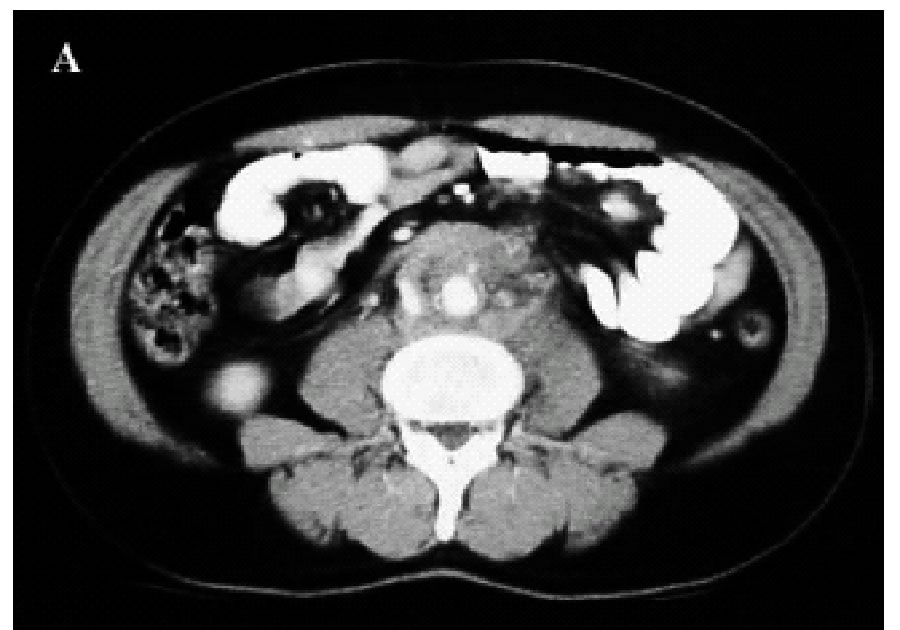

Figura 1. A-C: Tc spirale con MdC; evidenza di tessuto fibroso in sede retroperitoneale disposto attorno all'aorta,alla vena cava inferiore e alla biforcazione iliaca.(Da referenza 30)